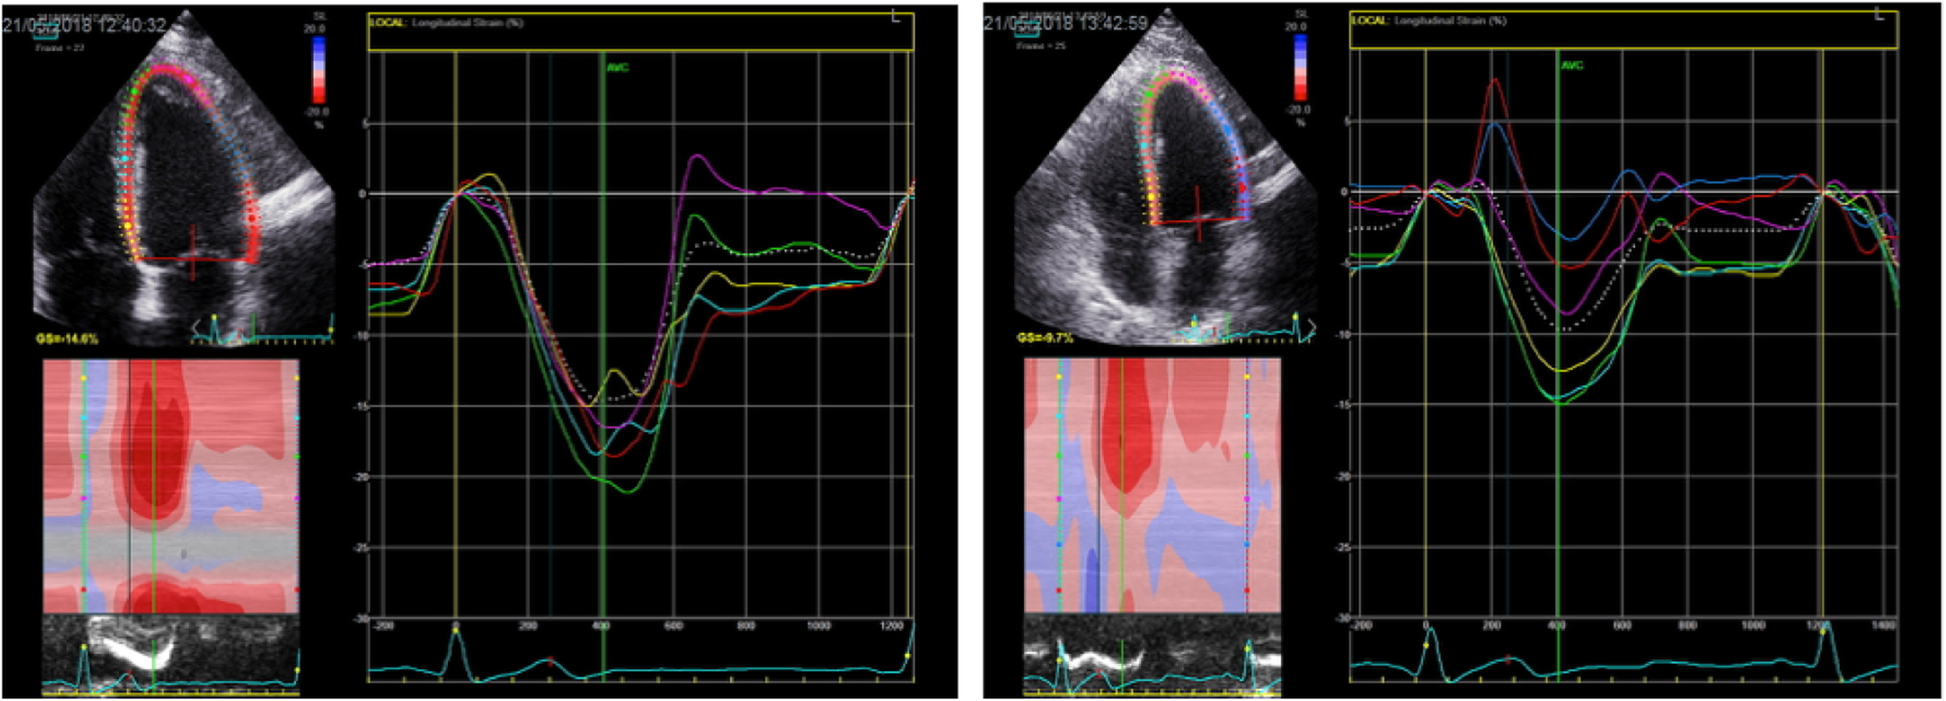

Fig. 3From: General anesthesia and positive pressure ventilation suppress left and right ventricular myocardial shortening in patients without myocardial disease – a strain echocardiography studyShows 4-chamber recordings of left ventricular global longitudinal strain before and after anaesthesia and positive pressure ventilation (PPV)Back to article page